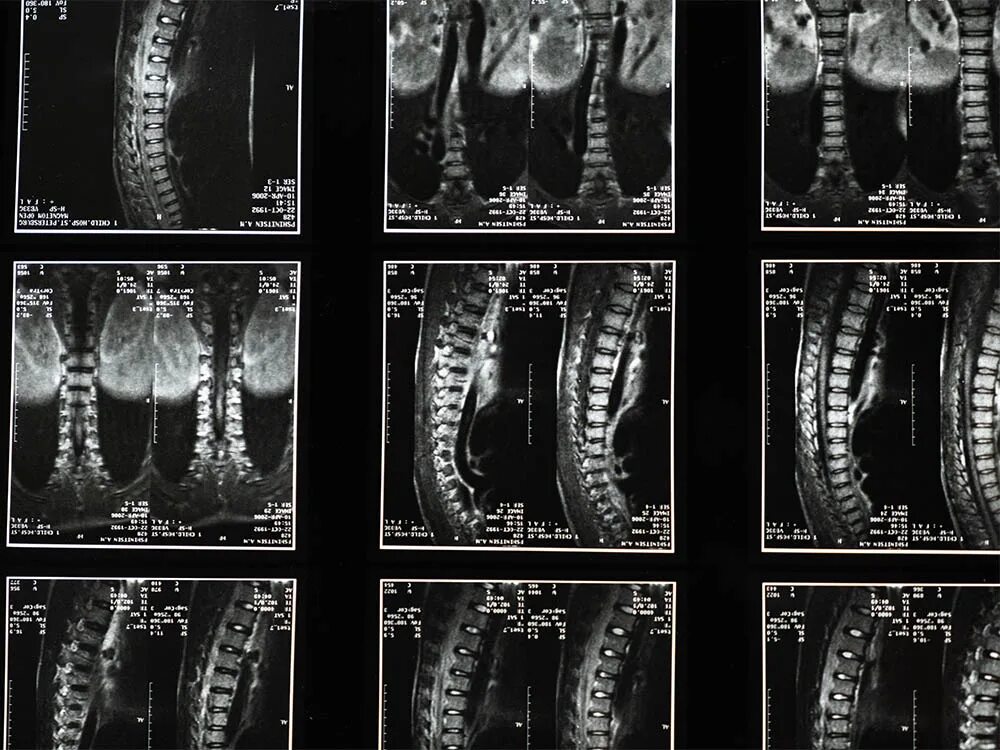

Мрт пояснично крестцового отдела тазобедренные суставы